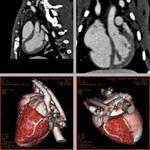

3D rabbit heart spiral CT images enhanced using the N1177 contrast agent.

N1177, an emulsified suspension that is composed of crystalline iodinated particles dispersed with surfactant, is being developed to visualize blood vessels and organs of the body, with particular interest in the arteries, veins and the heart chambers using a technique known as CT angiography (CTA). N1177 also accumulates in macrophage cells allowing for their detection with CT.

By comparison, CT offers to detect macrophage-rich lesions as early as two hours after the intravenous injection of N1177 with a spatial resolution allowing for the evaluation of coronary atherosclerotic plaques. Quantification of N1177 accumulation in atherosclerotic plaques is facilitated by the linear relationship existing between iodine concentration in tissue and signal increase measured with CT. In addition, detection of macrophages with N1177 could be used in connection with other CT markers identified in ruptured plaques such as areas of low densities, positive remodeling and absence of calcifications to enhance the potential of CT to identify high-risk plaques.